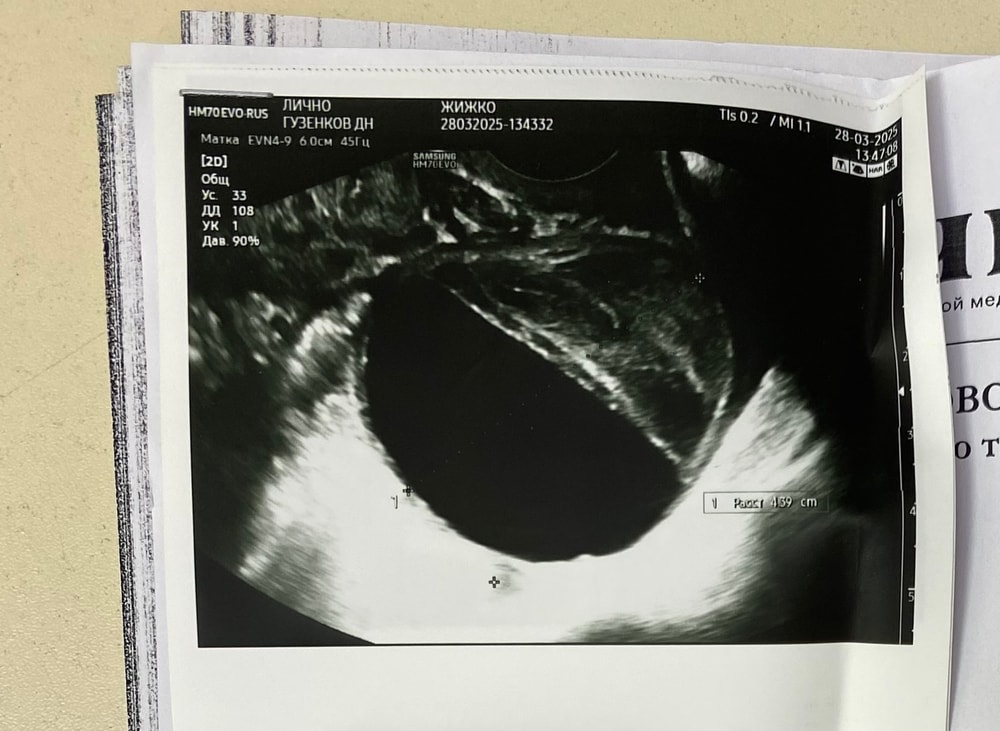

Алина, содержимое неоднородное - жидкость плюс пристеночный компонент с фибрином, это для ж/т характерно

Алина, нет, снимок вполне четкий. В любом случае, переделайте в динамике - после окончания менструации. Киста или исчезнет, или уменьшится

Марина Алташина, у меня она неделю назад была 38 мм, а вчера 43 мм, может жт расти?

Алина, ну, 38 и 43 мм - не большая разница. Измерение в немного другой плоскости. А так да, ж/т меняется по дням цикла

Екатерина, на одном узи сказали что киста жт на тот момент она была 3,8 см. На втором узи вчера, получается на 7 дпо, сказал врач что фолликулярная , но в заключении написал что киста желтого тела, вот для меня загадка теперь🤦‍♀️

Внутри типа нитей фибрины или как там правильно пишется, скорее всего киста жт.